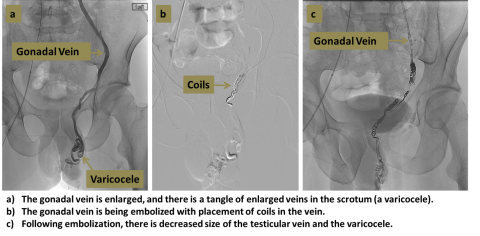

A varicocele is a dilated network of veins which occurs in the scrotum, usually on the left side, which can cause pain, swelling, and reduced fertility. Varicocele embolization is a minimally-invasive method of blocking these veins, which relieves these symptoms in a large proportion of patients.

An interventional radiologist uses ultrasound and X-rays to guide a catheter from the femoral vein in the groin into the gonadal vein (the source of the varicocele). Contrast injection is used to map the vein, and the vein is then occluded by using coils, sclerosants, or other agents.